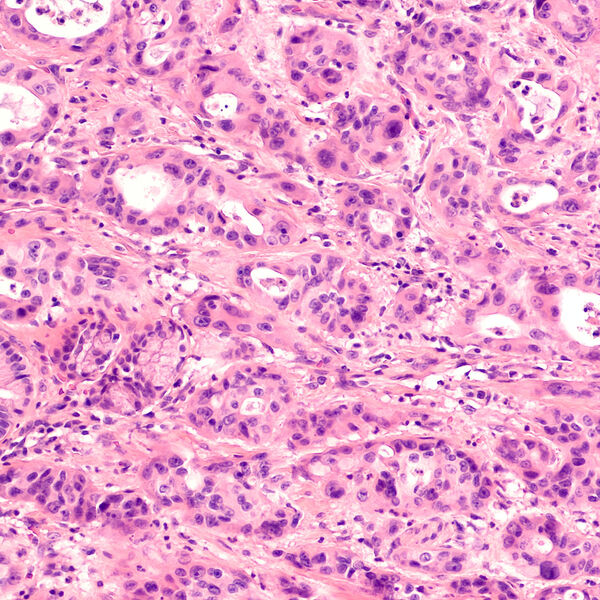

В число лидеров по самой высокой «агрессивности» и плохим прогнозам попала и меланома. Это очень опасный рак кожи, который может развиться в результате злокачественного перерождения меланоцитов. По данным ВОЗ, ежегодно в мире диагностируется около 130 тысяч новых случаев, а в России — порядка 12 тысяч.

Опасность меланомы — в ее стремительном развитии и высоком риске рецидивов. У 50% пациентов болезнь возвращается в течение года после завершения лечения. Однако в последние десятилетия благодаря появлению прогрессивных методик лечения — конъюгатов и иммунотерапии — многие пациенты с меланомой благополучно излечиваются.

Замыкает список опасных онкозаболеваний глиобластома — злокачественная опухоль головного мозга. На ее долю приходится до 40% всех опухолей мозга. Этот рак отличается крайне неблагоприятным прогнозом, поскольку современные методы лечения, включая лучевую и химиотерапию, обеспечивают выживаемость в диапазоне от года до двух лет. А средняя продолжительность жизни пожилых пациентов — не более полугода.